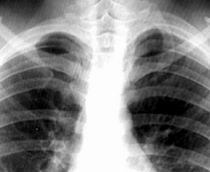

Cardiogenic pulmonary edema progession:

® vascular redistribution

® interstitial pulmonary edema (perihilar haze, peribronch cuffing, Kerley A & B lines)

® alveolar pulmonary edema

® pleural effusion

In CHF, there is progression from

Vascular congestion (recognized as prominent pulmonary veins)

cephalisation.

Next, interstitial edema and increased lymph flow manifests itself as Kerley lines.

Next, basal congestion with smaller lungs due to increased elastic recoil. Congested, boggy Liver also pushes the diaphragm up.

Lastly, full-blown pulmonary edema: acute diffuse alveolar pattern